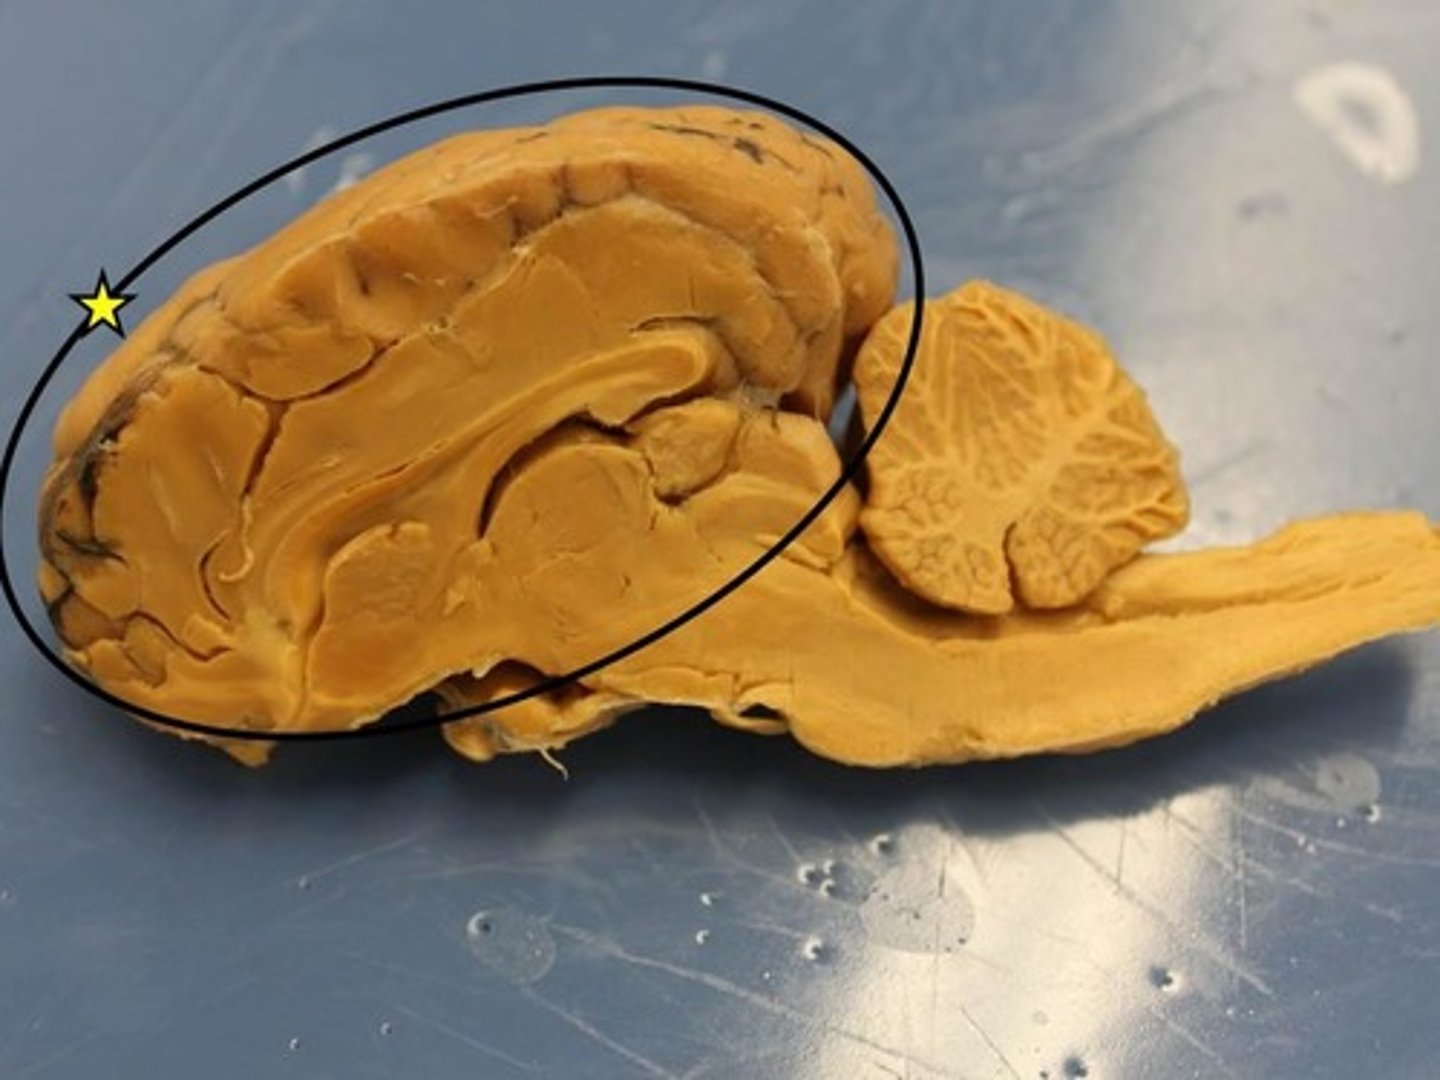

Cerebrum

Cerebellum

Vermis of the cerebellum

Arbor vitae

Corpus Callosum

Thalamus

Hypothalamus